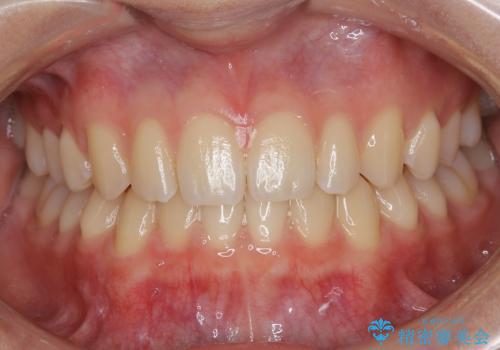

[ セラミック治療 ] 前歯の見た目を改善したい

![[ セラミック治療 ] 前歯の見た目を改善したいの症例 治療前](https://seimitsushinbi.jp/wp/wp-content/uploads/2025/10/IMG_9990-2-500x350.jpg?v=1761816440)

![[ セラミック治療 ] 前歯の見た目を改善したいの症例 治療後](https://seimitsushinbi.jp/wp/wp-content/uploads/2025/10/IMG_9934-500x350.jpg?v=1761816431)